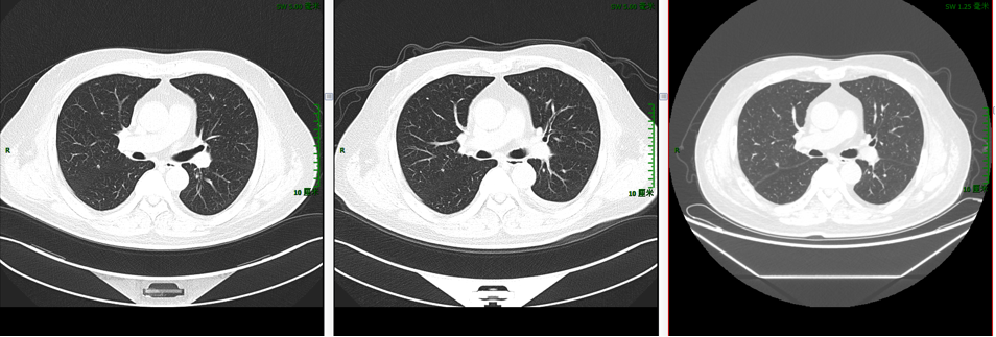

2020-3-6 胸部CT:两肺多发小斑点灶及微小结节,直径约3-10mm,较前(2019-11-05)部分增大。评估病情PD。

【TAS-102+呋喹替尼】2021-6-11 上腹部MRI提示“直肠CA根治术+肝转移瘤切除术+胆囊切除术”后改变,肝右叶肿瘤介入术后,肝右叶部分病灶较前(2020-12-2)范围缩小,部分病灶较前为新增,肝门区及后腹膜处多发肿大淋巴结,肝右叶见结节、斑片灶,较大者直径约35mm;胸部CT提示右肺上叶斜裂胸膜下结节,较前(2021-2-10)病灶内小空泡消失。两肺多发小斑点灶及小结节,较前部分有所减小,期间有肿瘤标志物进行性升高。

2021-12-7 胸部CT:右肺上叶斜裂胸膜下结节,较前缩小。